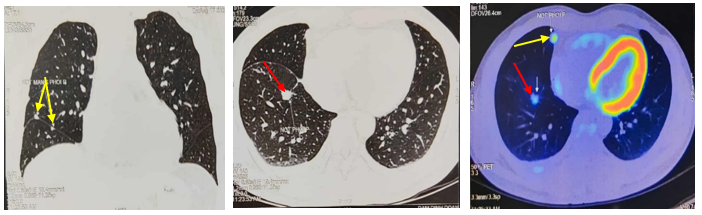

Chụp cắt lớp vi tính lồng ngực: Hình ảnh các nốt kính mờ rãnh liên thùy và màng phổi phải kích thước 2x3mm. Đám dải xẹp phổi thùy giữa phổi phải

Hình 6: Hình ảnh chụp cắt lớp vi tính lồng ngực: nốt tổn thương u phổi phải nhỏ hơn ban đầu sau 3 tháng điều trị (mũi tên vàng)

Chụp cắt lớp vi tính ổ bụng: Không phát hiện tổn thương

Đánh giá: Bệnh đáp ứng 1 phần

Điều trị tiếp: Alectinib 600mg/lần x 2 lần/ngày,uống trong bữa ăn

Chụp cắt lớp vi tính lồng ngực: Hình ảnh các nốt kính mờ rãnh liên thùy và màng phổi phải.Đám dải xẹp phổi thùy giữa phổi phải

Hình 7: Hình ảnh chụp cắt lớp vi tính lồng ngực sau điều trị, tổn thương u giảm kích thước sau 6 tháng điều trị (mũi tên vàng)

Chụp cắt lớp vi tính lồng ngực: Hình ảnh các nốt kính mờ rãnh liên thùy và màng phổi phải. Đám dải xẹp phổi thùy giữa phổi phải

Hình 8: Hình ảnh chụp cắt lớp vi tính lồng ngực sau 9 tháng điều trị

Điều trị tiếp: Alectinib 600mg/lần x 2 lần/ngày, uống trong bữa ăn